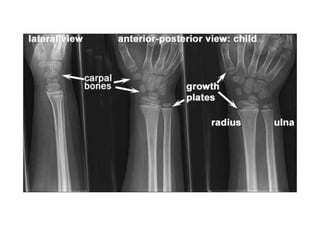

RADIOLOGIA DO

TRAUMA DO ESQUELETO

Referência: http://www.accessexcellence.org/RC/VL/